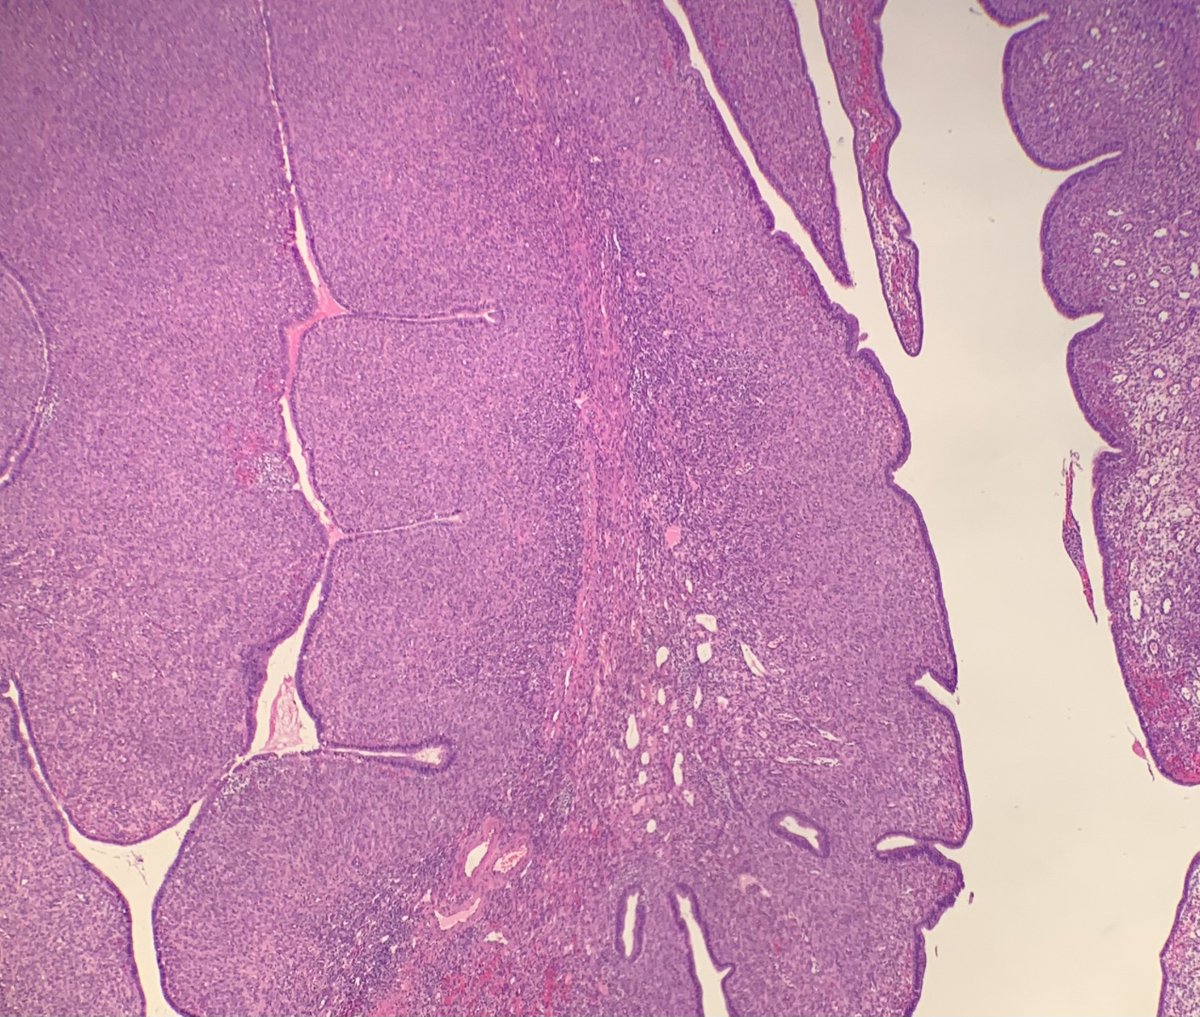

60-year-old man with an incidental mediastinal mass. What is the diagnosis? A) True thymic hyperplasia B) Thymic follicular hyperplasia C) Thymoma ─ Type AB D) Micronodular thymoma with lymphoid stroma #Pathology #PathTwitter